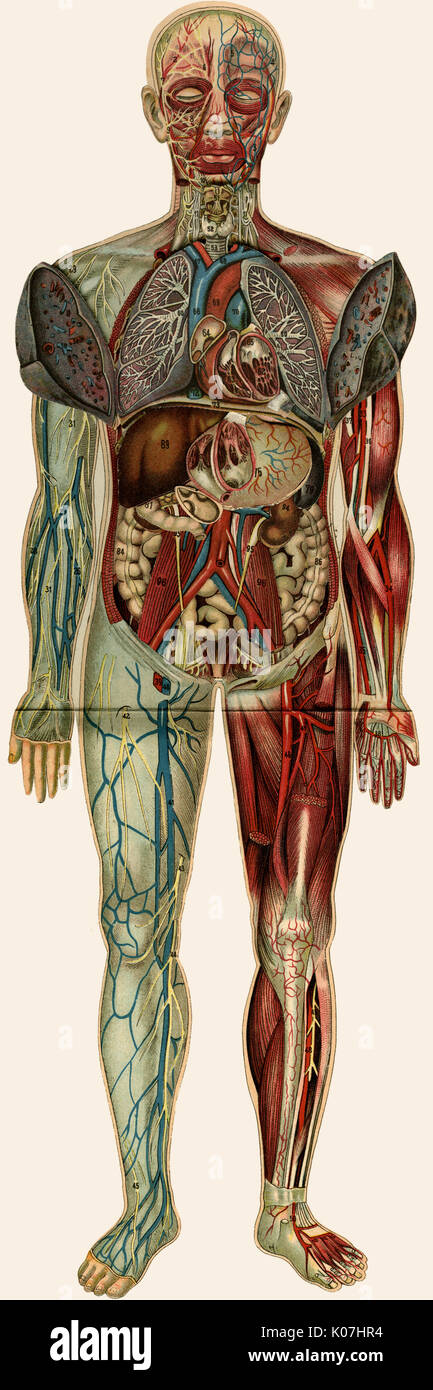

RMB2J4C6–Medizin, Anatomie, männlichen Körper, Kupferstich von J.Remmelin, 18. Jahrhundert, private Sammlung, Menschliche Körper, Organe, Okkultismus, historisch, historische, Personen, Artist's Urheberrecht nicht geklärt zu werden.